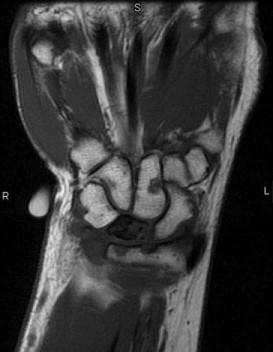

问题 女,41岁,纺织工,腕部痛无力数周,请结合CR和MR,选出最可能的诊断 ( )

选项 A、骨髓炎 B、骨软骨炎 C、月骨缺血坏死 D、骨质疏松 E、月骨结核

答案 C